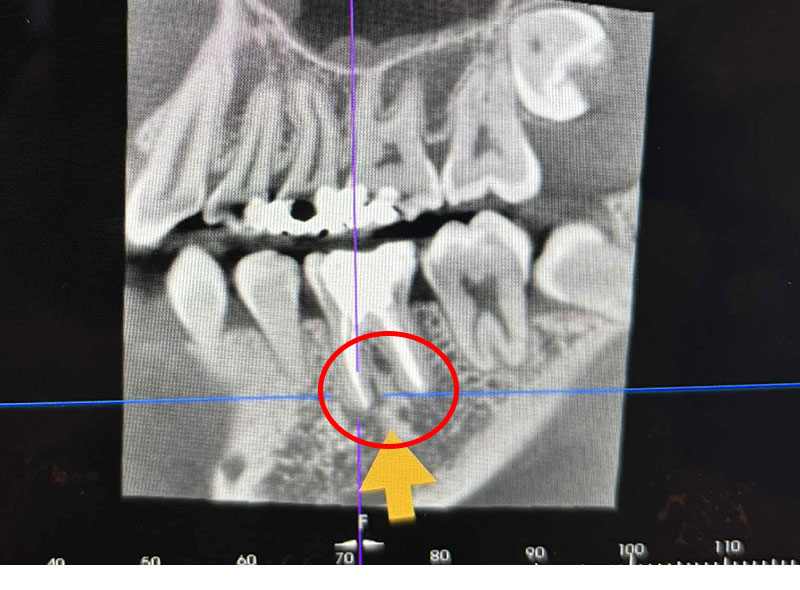

歯科用CTで症状を立体的に把握

症状によっては、従来のレントゲンだけでは判断できない原因が隠れている場合があります。歯科用CTは立体的(3D)で根管の状態を把握できるため、必要に応じて歯科用CTを活用し、根本原因を捉えてから適切な治療を行います。

Step01歯科用CTを使用した検査・治療計画の立案

歯科用CTを使用して、歯と歯根の詳細な3D画像を撮影し、正確な診断を行います。CTは根管の形態や歯根破折の有無を判断するのに役立ち、適切な治療計画を作成するためには必要不可欠です。検査結果により、歯根破折が認められる場合は抜歯やインプラント等の代替治療を提案いたします。